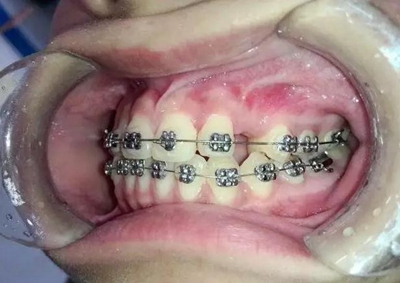

14歲,牙齒嚴(yán)重?fù)頂D,上頜兩個(gè)尖牙在側(cè)切牙唇側(cè)

采用細(xì)絲排齊,8字結(jié)扎控制尖牙,此時(shí)如果直接拉尖牙,勢必導(dǎo)致上頜磨牙近中移動(dòng),更何況磨牙本來就是遠(yuǎn)中關(guān)系,需要強(qiáng)支抗。

幾個(gè)月后,換上不銹鋼方絲,側(cè)切牙遠(yuǎn)中彎制了一個(gè)內(nèi)展彎,避免了尖牙遠(yuǎn)中移動(dòng)時(shí)與弓絲形成頜干擾。

考慮了一下沒有采用其他輔助裝置和種植支抗,還是采用輔弓增加支抗,經(jīng)濟(jì)適用,也便與操作,0.8不銹鋼絲彎制,進(jìn)行熱處理,增加其彈力。

結(jié)扎固定后開始牽引尖牙向遠(yuǎn)中,

兩個(gè)月后效果還是比較明顯的。